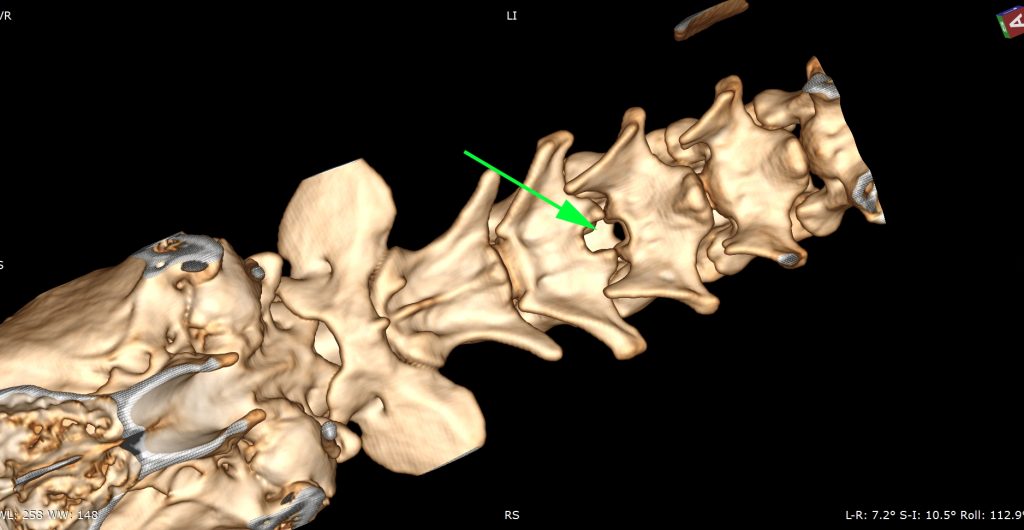

Hernie très compressive C3-C4 sur un Beagle.

Scanner de contrôle postopératoire en reconstruction tridimensionnelle.

• En neurologie et neurochirurgie, le scanner est très performant pour l’exploration des affections d’origine osseuse ou discale. Il permet de détecter les hernies discales calcifiées, les malformations vertébrales, les fractures vertébrales, les instabilités, ainsi que certaines compressions médullaires d’origine osseuse. Il est également utile pour l’exploration de certaines affections intracrâniennes, notamment lorsqu’elles impliquent des structures osseuses.